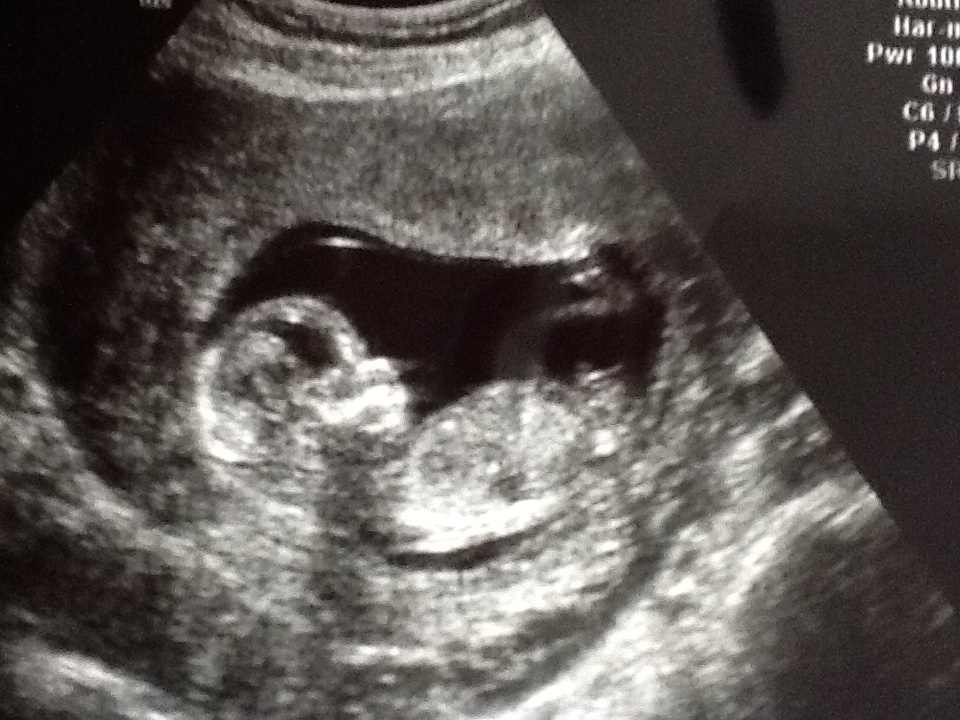

13 weeks and 0 days nub shots, tell me what you think!

bottom one does look more pink than blue, and no nub in the top pic!

Looks girlie from second pic. But not the best shots.....

Girl skull, goodluck.